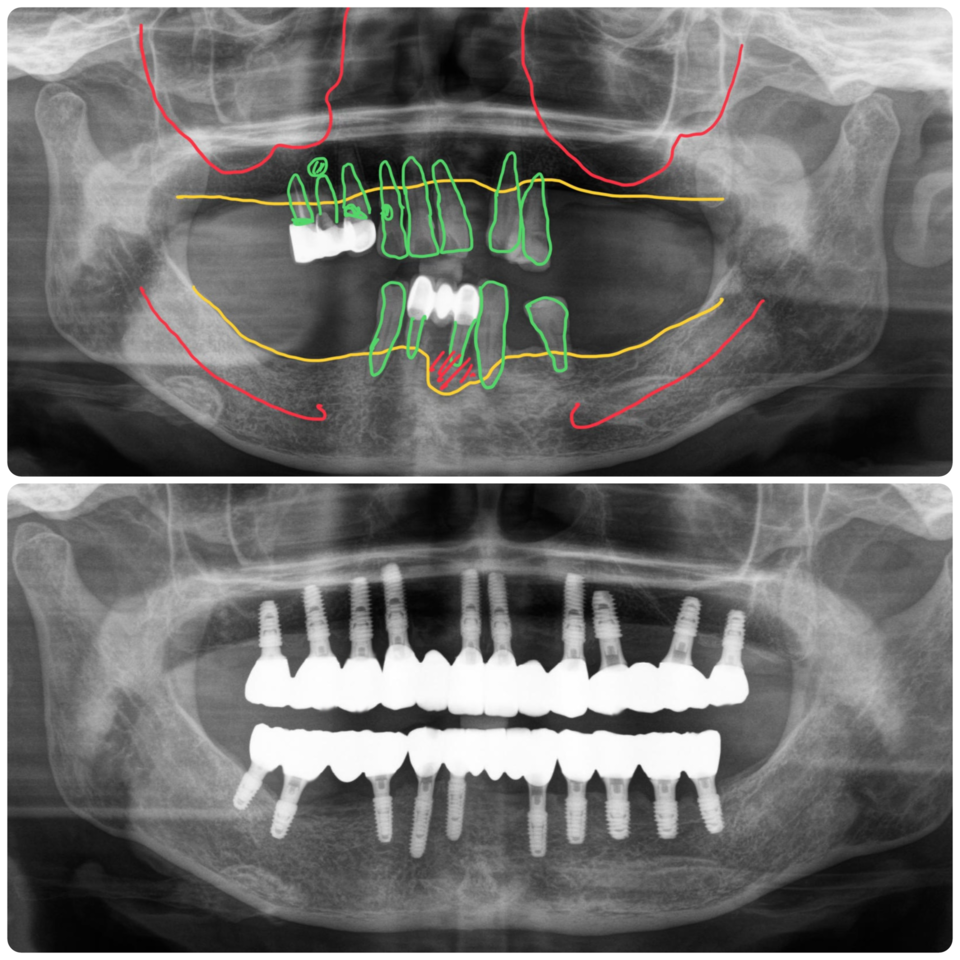

상악에는 10개, 하악에는 10개 식립 수술당일 임시치아

상악에 총 10개의 임플란트를 식립했어요. 우측 어금니 부위에는 본인의 뼈를 이용해서 상악동 리프팅을 간단하게 시행해서 초기고정이 나와서 임시치아에 포함시켰습니다.

좌측 어금니 부위에는 골이식량이 많고 고정이 충분하지 않아서 뼈이식과 함께 임플란트를 식립했지만 잇몸 속에 임플란트를 넣어 두어 외부 자극으로부터 보호해 주었습니다.

위 8, 아래 10개의 임플란트에 지대주를 연결해서 수술당일 임시치아를 해 드렸어요. 골밀도가 떨어져서 고정이 걱정되었지만 수술이 잘되어서 임시치아를 적용할 수 있었습니다.